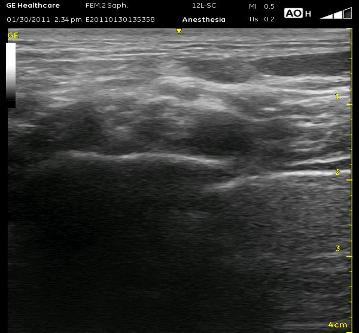

Above, you can see a needle advancing from the left of the image and piercing the middle scalene muscle to approach the ‘corner pocket’ at 2 cm depth. The muscle is indistinct due to the very steep angle at which it is being viewed. The ‘corner pocket’ is at the intersection of the rib, artery and the plexus. A single bolus here is almost always sufficient, however, if the neural elements are seen past the 2 o’ clock position or you need a really quick set-up for the radial aspect of the hand, it is best to inject more in the center of the plexus. Either way, stay away from multiple passes as small vessels can be all around, and it is just not necessary. More on this later…

lateral end of the probe posteriorly a few cm in order to see the artery and the neural elements ‘end-on’. I don’t bother trying to identify which DIVISIONS I see though it is possible to recognize at times a clear anterior ‘cluster’ and posterior ‘cluster’. The neural elements should be posterior and superior to the artery (though I have seen them rolled anterior and superior to the artery) and appear as white borders around a dark center as there is relatively little connective tissue present at this distance. I will guide my needle between the middle scalene muscle and the divisions toward the ‘corner pocket’ which is the intersection of the first rib, neural elements and subclavian artery. Sometimes hydrodissection is helpful to push the divisions superiorly and out of the way of the needle. Seeing them being pushed upward is a good confirmation that the block will be successful.

I always recommend a PAUSE to look for bouncing arterial vessels and a quick decrease in manual PRESSURE to identify compressible venous flow before entering with the localizing needle for all blocks. Here, I also tell people to pause to make sure they’ve correctly identified the pleura and first rib. The widely ovoid structure in the upper right-hand corner is the omohyoid muscle which can appear as a vessel. Further, vessels may often be seen in this area tracking to the left across your intended needle path.

In the right-sided ultrasound picture below, the divisions are just to the left of center above the bright white line with a dark shadow below it. That dark line is the first rib. The almost triangle-shaped structure to the left above that line is the middle scalene muscle. The pleura can be seen as the bright white line to the right with the ‘comet tail’ of white reflections deep to it. Of course, it is moving and has a glistening effect in real time scanning, but it can be mistaken for the first rib. The pleura has these characteristics and is usually seen deep to the first rib, but it can appear above it and seem to have the artery resting on it. See if you can recognize the structures on the ultrasound image below, then look at the next image for the answers and to see the proper needle orientation.